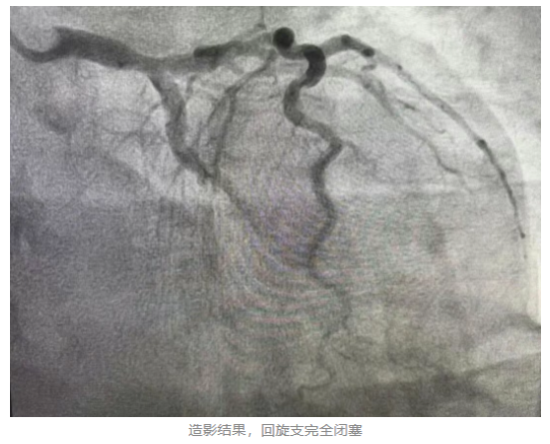

心血管内一科主任张国华到场后,结合患者心电图报告、临床症状及既往心脏病史,迅速诊断其为急性心肌梗死,并指导立即给予口服药物,建议其进行急诊冠脉造影检查及介入治疗开通血管。心血管内科介入团队迅速为李先生进行冠脉造影检查。检查结果显示,患者左冠状动脉回旋支完全闭塞,随时可能危及生命。经过血栓抽吸后血管开通,但病变处狭窄仍为95%。随后心血管内一科介入团队又为患者植入1枚支架。支架植入后患者病变狭窄完全消失,血流通畅,胸痛消失,意识状态恢复。